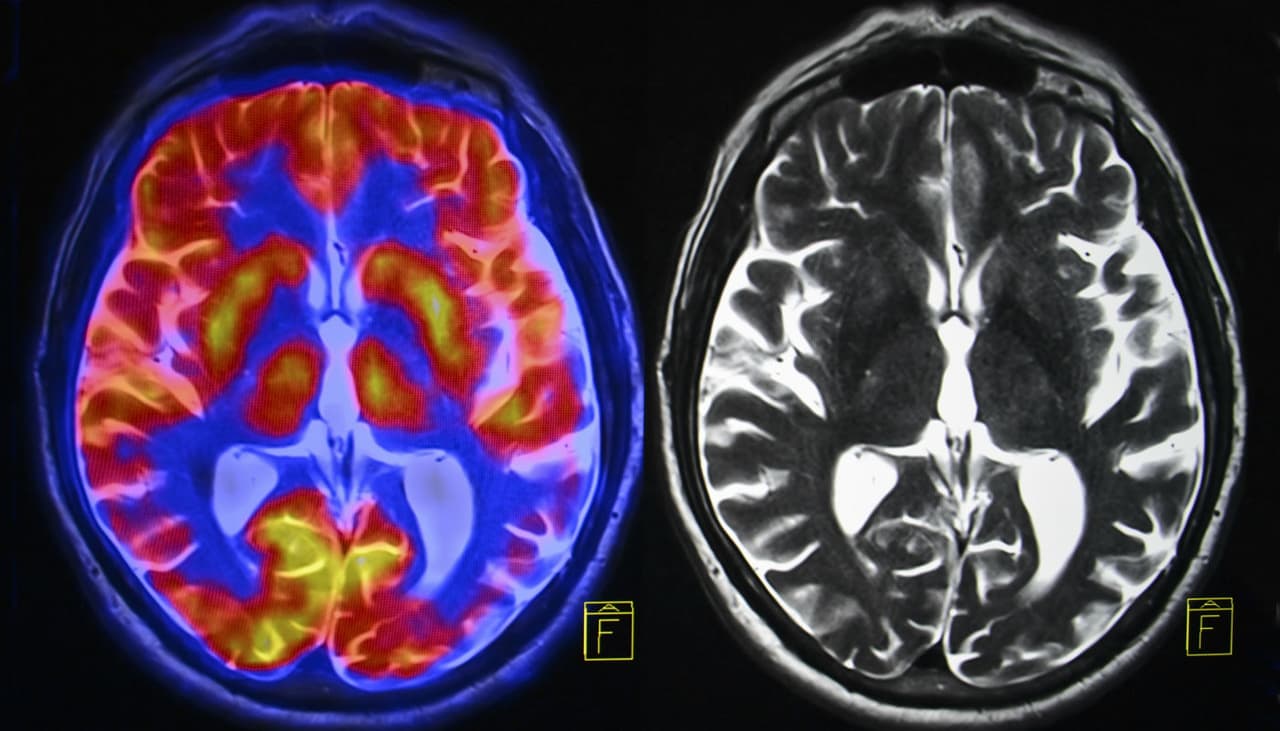

«Esto tiene sentido porque se sabe que el bulbo olfatorio (relacionado con el sentido del olfato) y el córtex entorrinal (relacionado con la memoria y la nomenclatura de olores) están entre las primeras estructuras cerebrales que son afectadas por la enfermedad.»